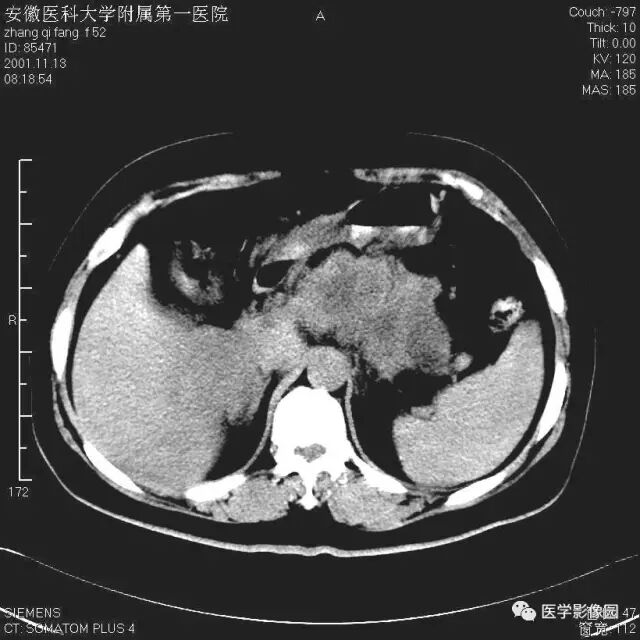

图6-4-13胰腺癌

CT平扫见胰体、尾部局限性肿大,

其内境界不清的低密度灶(↑);

肝右叶有多个低密度转移灶(长↑),

并见腹水